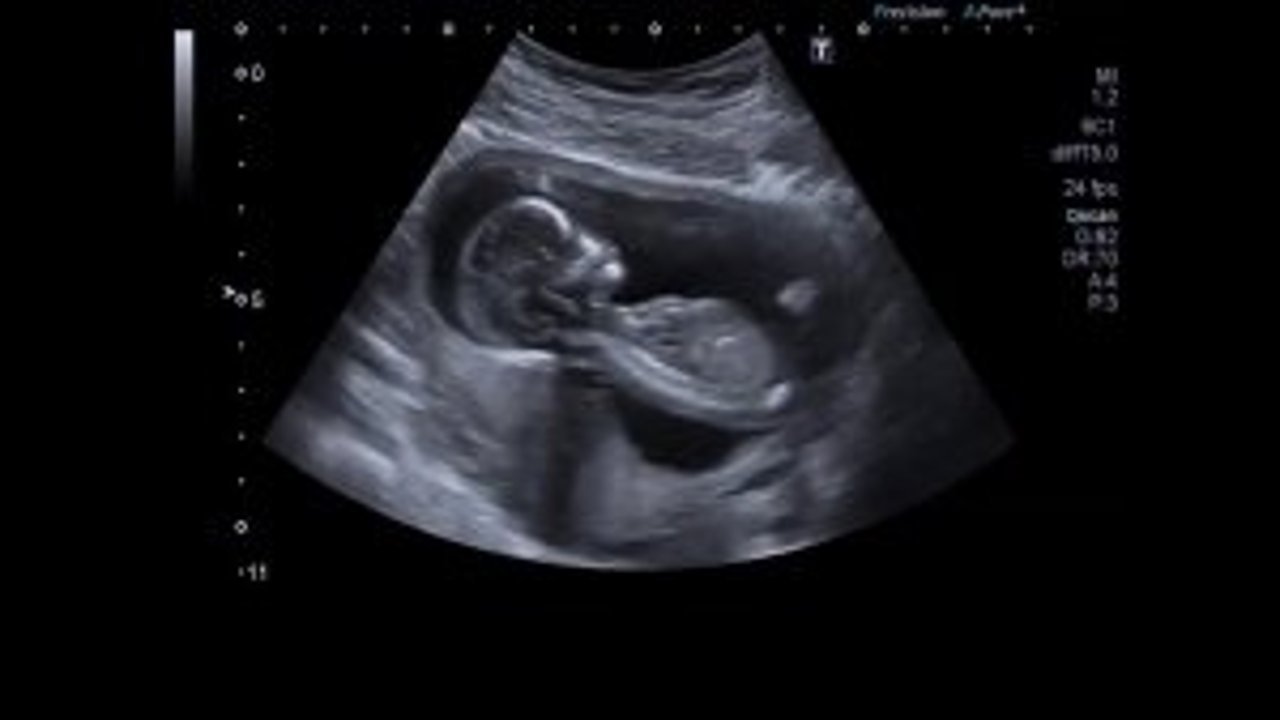

Tüp Bebek ve Kısırlık Uzmanı Doç. Dr. Adnan Yener Kahramanmaraş’ta başarılı çalışmalarına bir yenisini daha ekledi.

Köşker ailesinin 5 yıllık çocuk hasretini son buldurdu